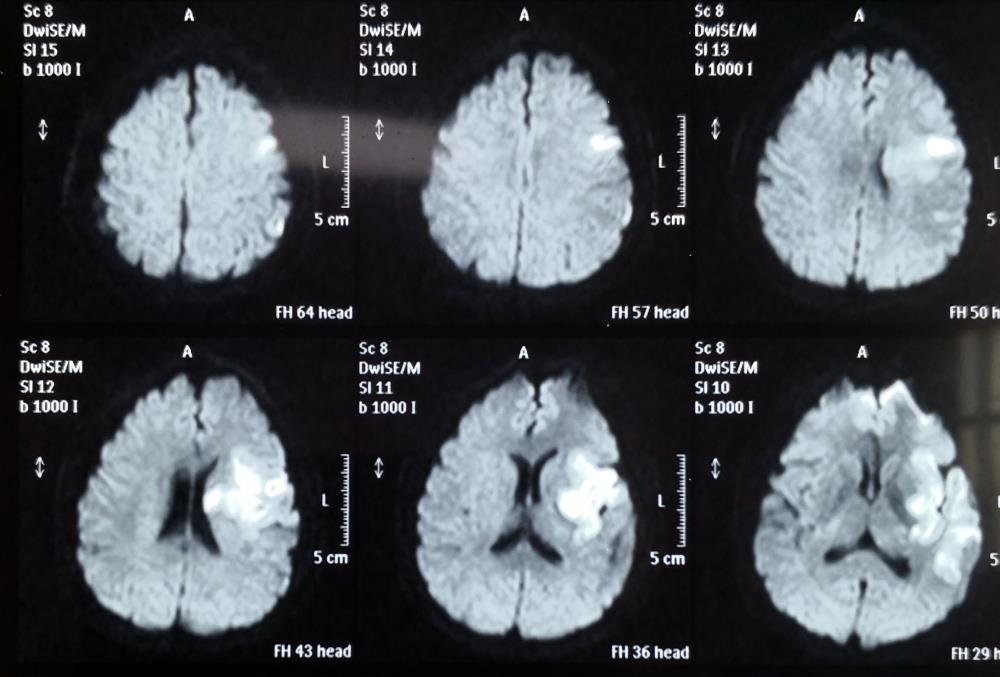

2020年12月14日上午9点左右,59岁的胡某在家中突然昏迷,由120送至榆林二院急诊,入院时患者神志模糊,四肢无法活动,不能言语。急诊行头颅DWI+MRA检查提示:左侧大脑半球新发大面积梗死,左侧大脑中动脉闭塞。

术前头颅DWI